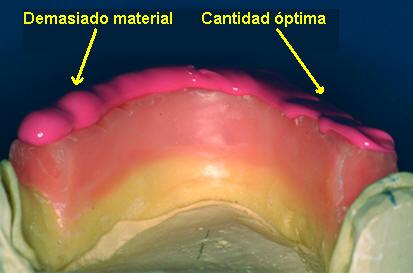

Dígale al paciente que abra la

boca y aplique una silicona para registro

en el rodete inferior y haga morder al paciente

hasta su endurecimiento, puede guiar el

movimiento de cierre con los dedos. (Ver imagen inferior)

El

material no debe desbordar los rodetes |

Registro en céntrica

con silicona para registro |

Demasiado material produce desbordamiento |